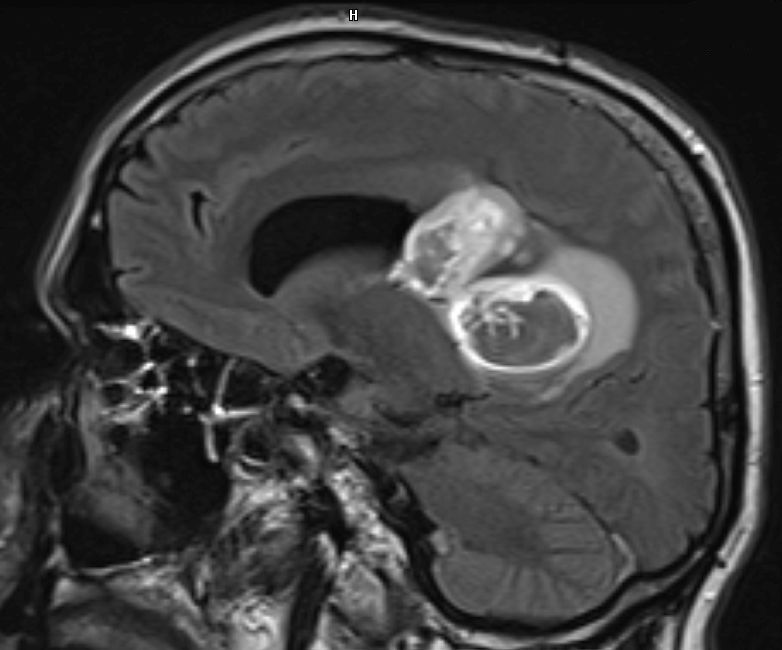

Zystisches Gliom parieto-occipital |

![]() |

![]() | ||